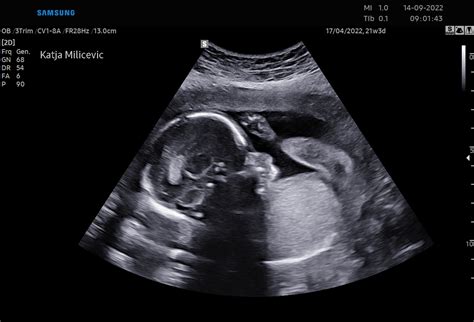

Ko se ženska obrne na ginekologa, bo ta najprej preveril osnovne podatke o ciklu in simptomih, nato opravil ginekološki pregled in po potrebi odvzel bris ali opravil ultrazvok. Ultrazvok je ključen za oceno položaja nosečnosti (v maternici ali zunaj nje), velikosti ploda in prisotnosti morebitnih težav, kot so miomi ali hematomi.